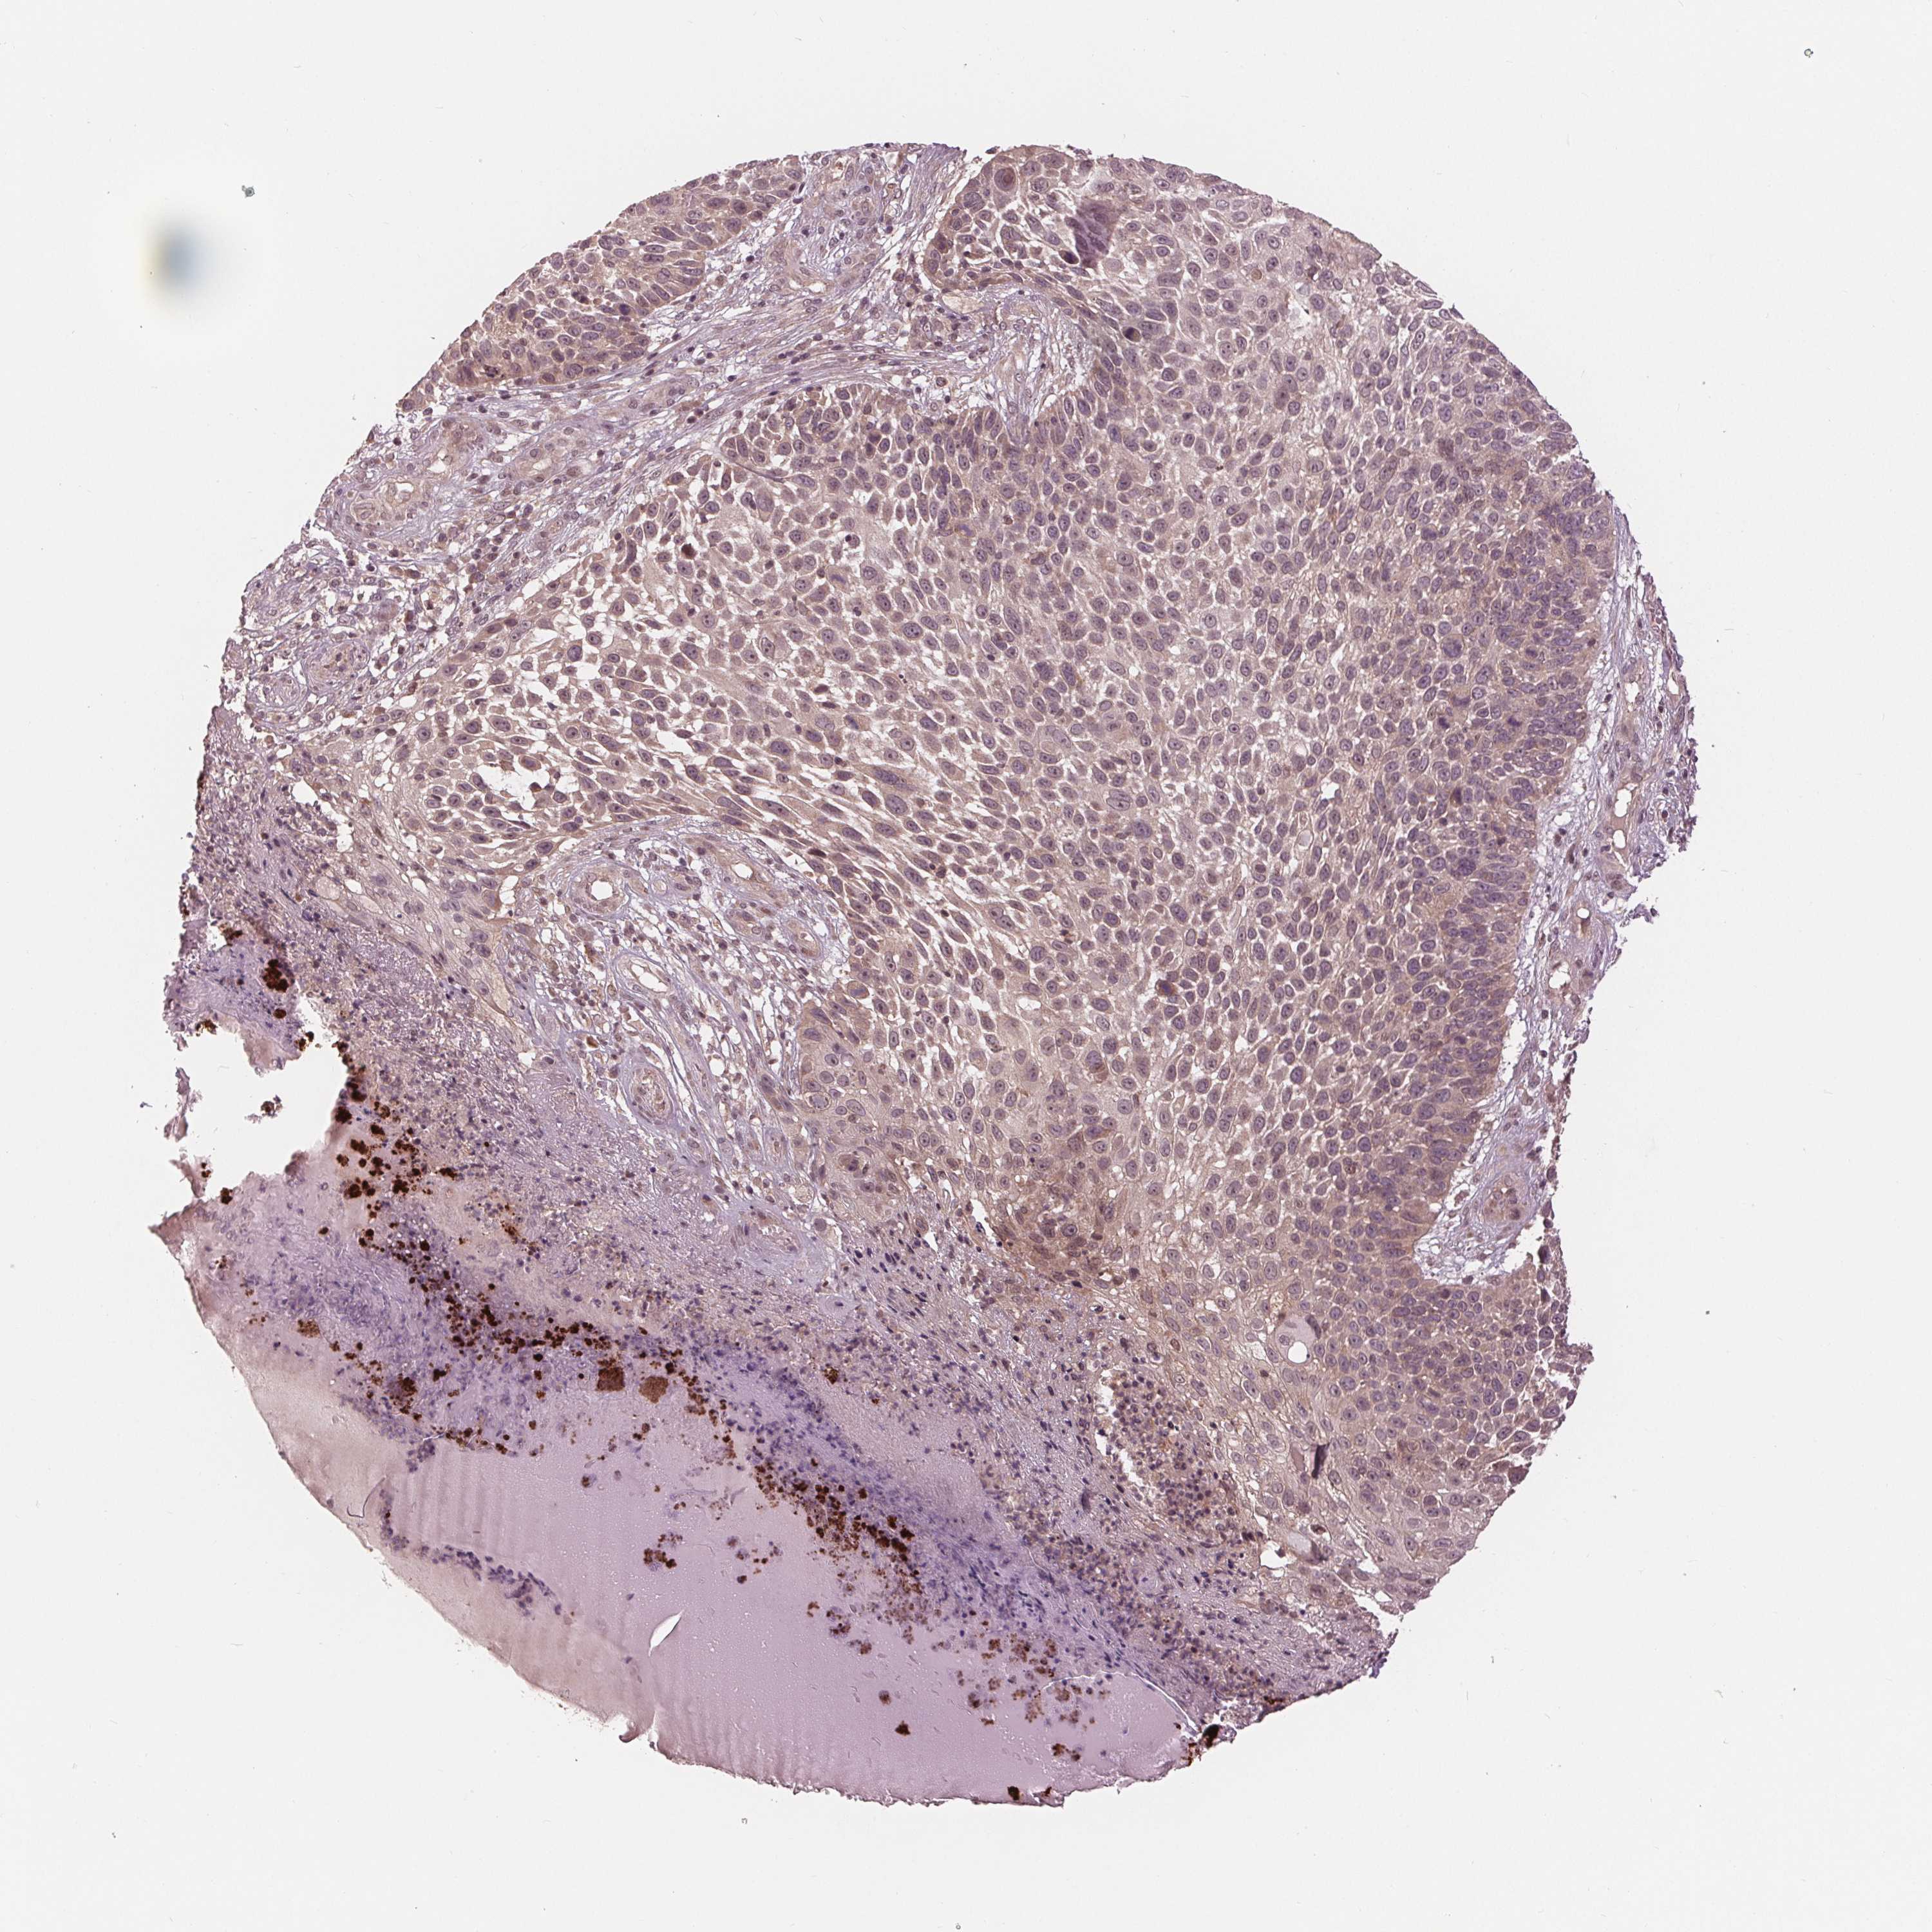

SKIN CANCER - Protein expressioni

A mouse-over function shows sample information and annotation data. Click on an image to view it in a full screen mode. Samples can be filtered based on level of antibody staining by selecting one or several of the following categories: high, medium, low and not detected. The assay and annotation is described here.

Each image is clickable and will lead to virtual microscopy that enables deeper exploration of all samples and also displays staining intensity scores, fraction scores and subcellular localization as well as patient and tissue information for each sample.

Antibody HPA066695

Staining

High

Medium

Low

Not detected

Intensity

Strong

Moderate

Weak

Negative

Quantity

>75%

75%-25%

<25%

None

Location

Nuclear

Cytoplasmic/membranous

Cytoplasmic/membranous,nuclear

Basal cell carcinoma